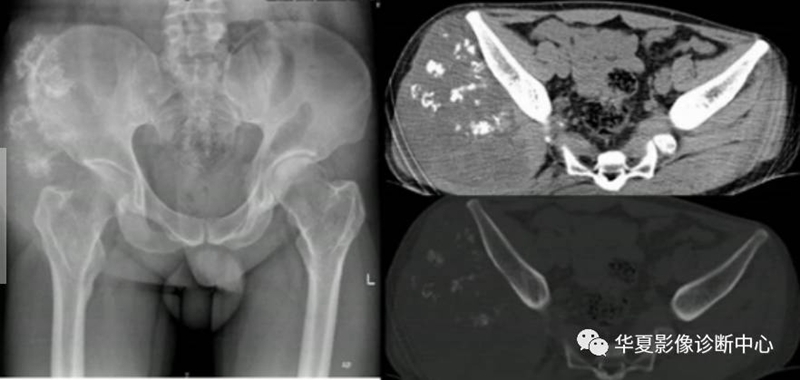

4、肿瘤软骨钙化

形态:环状,弧状,点状具有诊断意义,大小,良性者形态完整,境界清楚,密度均匀。恶性者相反。(如下图)